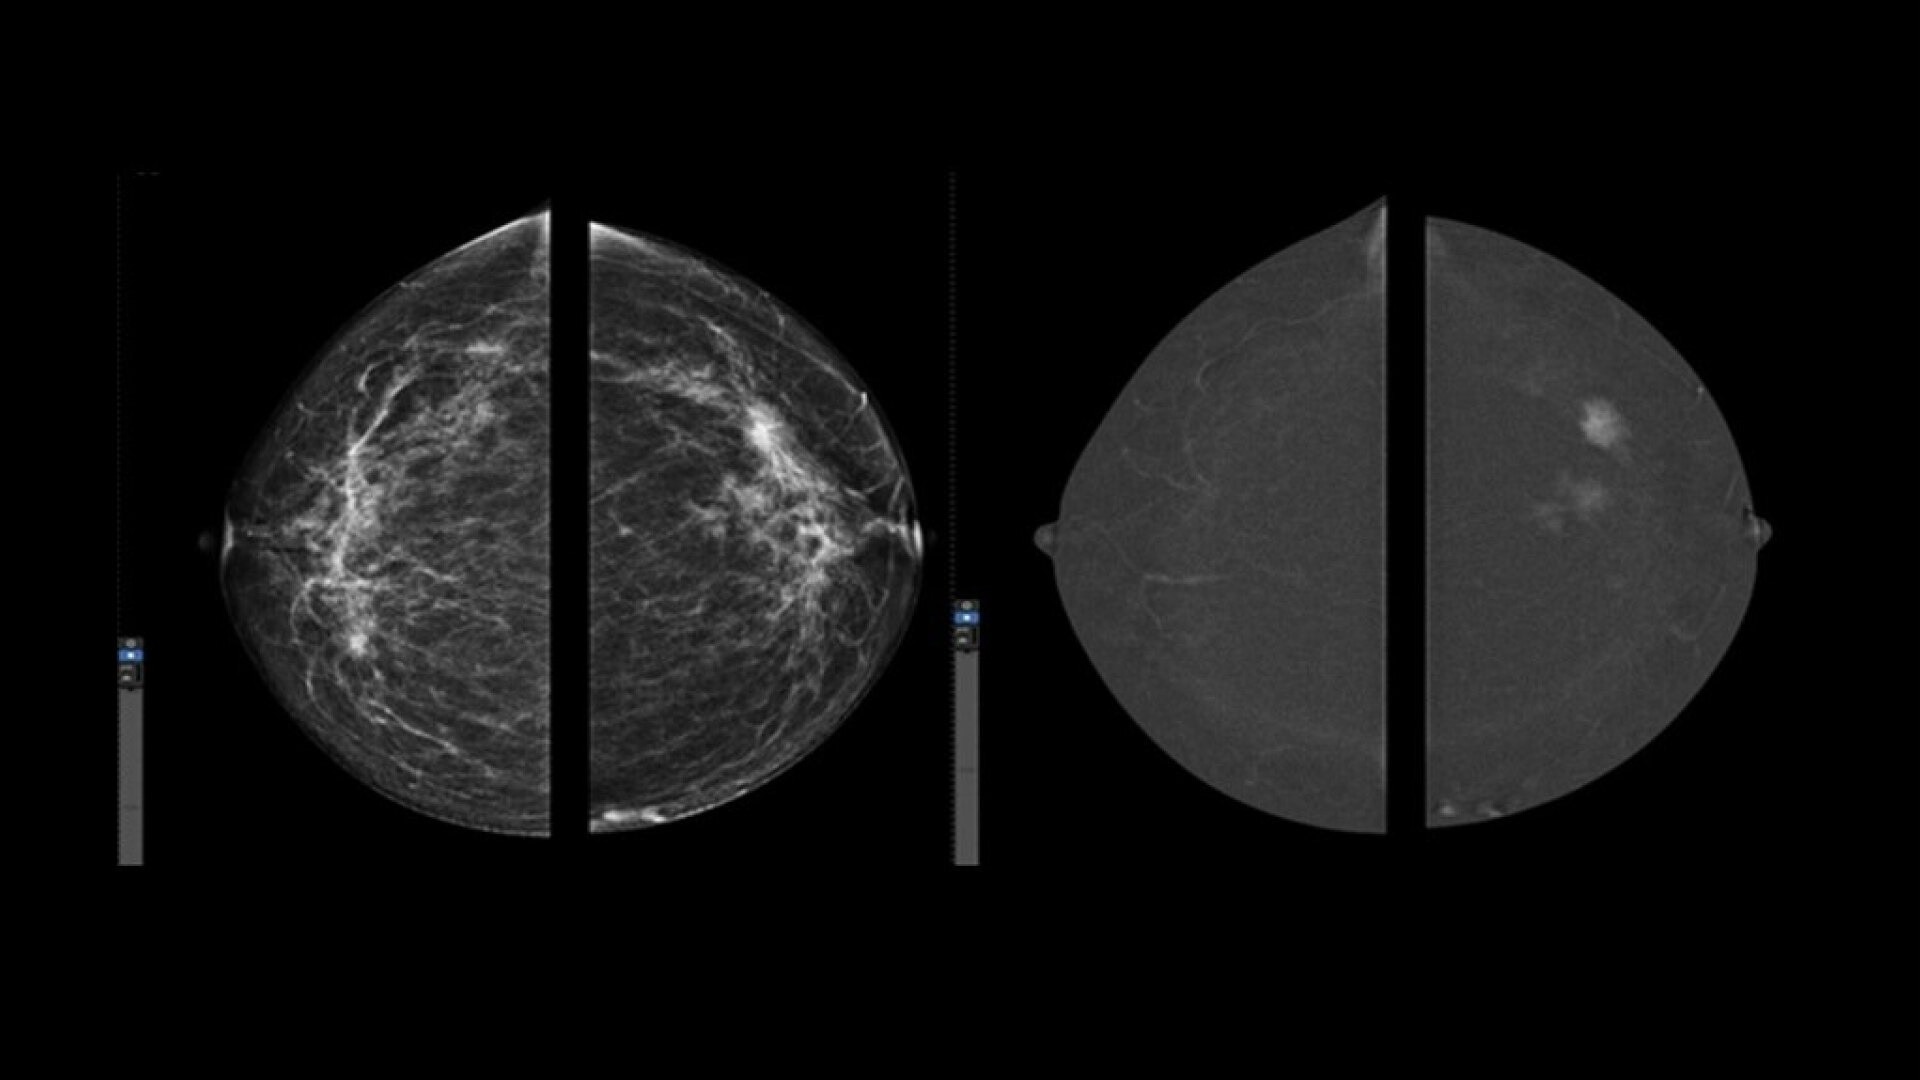

• Helps reduce the masking effect of fibroglandular breast tissue and increases the tumour signal1.

• Contrast agent highlights areas of unusual blood flow.

• CEM is an alternative imaging method to MRI, especially when MRI availability is limited, and for patients for whom MRI is contraindicated5.